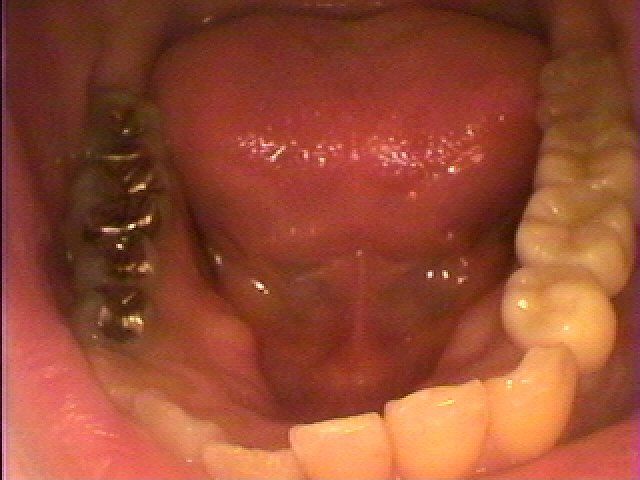

抜歯時になります

数週間待って傷が治りブリッジかインプラントかをそれまでにお話をさせていただき今回はブリッジにて機能回復を行うようになりました